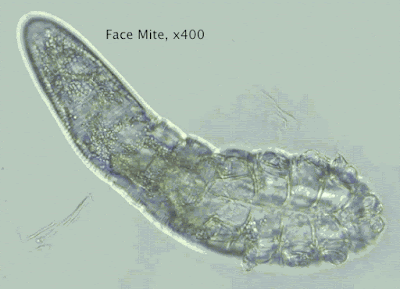

Πρότυπα Κέντρα Θεραπείας Demodex, Βλεφαρίτιδας, Ξηροφθαλμίας, Χαλαζίων, Δυσλειτουργίας Μεϊβομιανών Αδένων